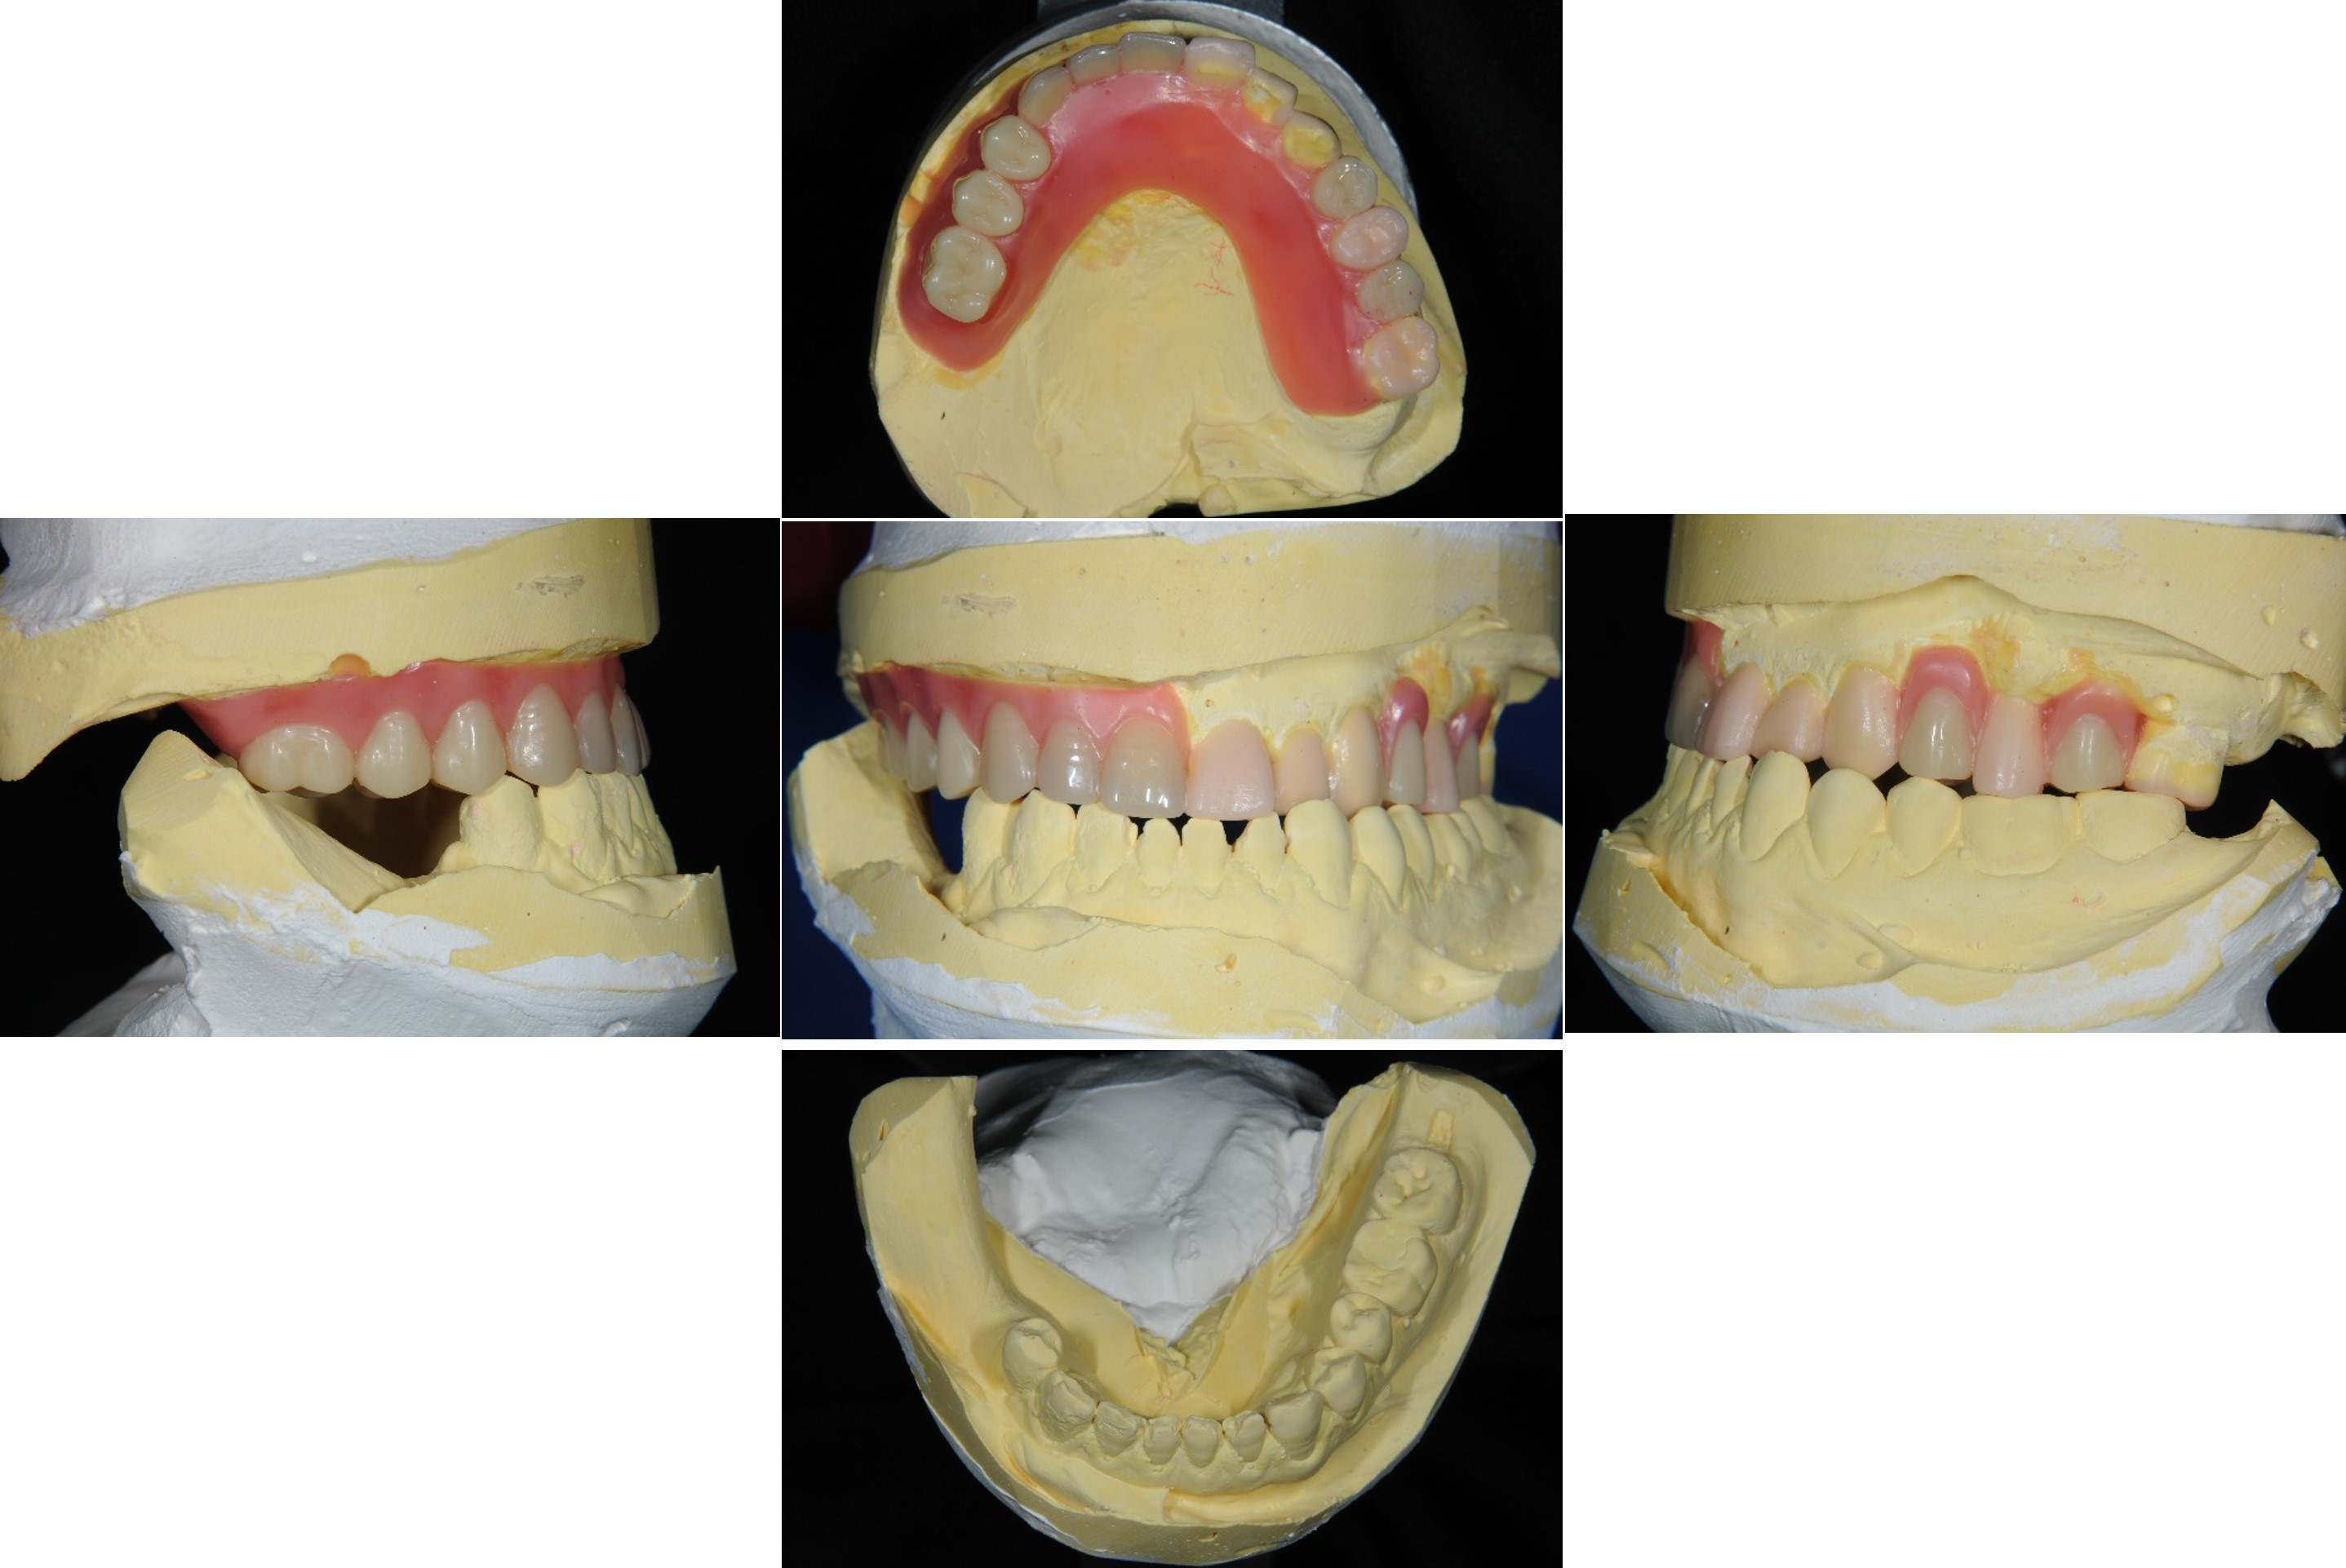

蠟牙製作

組合後外冠及活假牙套件

外冠及活動假牙套件

活動假牙套件

正式假牙完成